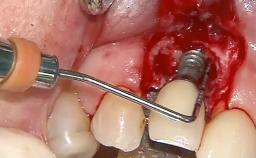

Occlusal Load—a Factor for Implant Failure?

In this case, Nicola Zitzmann describes the sudden loss of a previously well-osseointegrated implant that had been in healthy function for 5 years. The case includes recommendations for occlusion and function of implant restorations. A 74-year-old patient had received implant-fixed dental prostheses in the maxilla in 2008, and in the right mandible three years later. His tooth loss was mainly related to recurrent caries associated with hyposalivation as a potential side effect of his cholesterol-lowering medication.